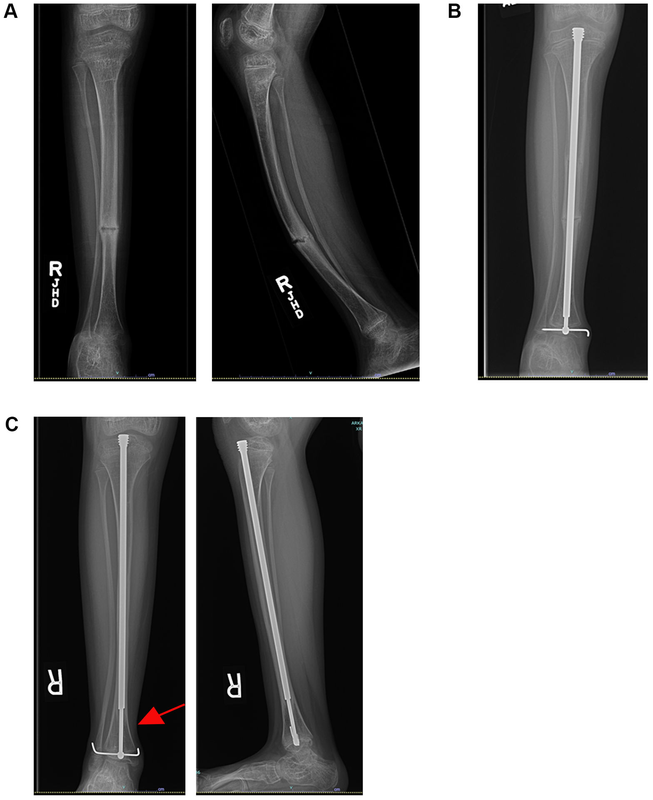

严重胫腓骨弯曲畸形

瓷娃娃,钢筋铁骨:成骨不全症(OI):临床特征和治疗的最新进展:2020年作者:RonitMarom,BrienMRabenhorst,RoyMorello作者单位:DepartmentofMolecularandHumanGenetics,BaylorCollegeofMedicine,Houston,Texas,USA.译者:陶可(北京大学人民医院骨关节科)摘要成骨不全症(osteogenesisimperfecta,OI)是一种遗传性骨骼发育不良,其特征是骨骼脆弱(脆性增加、易发生骨折)和骨骼畸形。虽然大多数病例与编码I型胶原蛋白的基因COL1A1和COL1A2的致病变异有关,但高达25%的病例与在胶原蛋白生物合成途径中发挥作用或参与成骨细胞分化和骨矿化的其他基因相关。临床上,成骨不全症(OI)具有异质性且严重程度不同。除了骨骼表现外,它还会影响多个系统,包括牙齿和颅面异常、肌肉无力、听力丧失、呼吸系统和心血管并发症。建议采用多学科护理方法,不仅要解决骨折、行动不便、生长和骨骼疼痛,还要解决其他骨骼外表现。虽然双膦酸盐仍然是治疗成骨不全症(OI)的主要药物,但正在探索新的策略,例如硬化蛋白抑制抗体和转化生长因子(TGF)β抑制,不仅可以解决低骨密度问题,还可以解决固有的骨脆性问题。动物模型研究扩大了对成骨不全症(OI)病理机制的理解,并且与正在进行的临床试验一起,将允许为这些患者开发更好的治疗方法。图1. 一名患有成骨不全症的8岁女孩有严重的胫骨前弓和复发性骨折(A)。该病例使用支具进行非手术治疗失败。患者接受了2节段开放式胫骨截骨术,并放置了Fassier-Duval伸缩棒(B)。患者现在手术已超过1年。注意棒的增长和伸缩(C-红色箭头)。截骨愈合良好,患者目前无症状。 3. 成骨不全症(OI)的治疗成骨不全症(OI)的管理主要是支持性和对症治疗,并根据患者的年龄、成骨不全症(OI)类型和严重程度个体化治疗。一些轻度I型成骨不全症(OI)患者可能只需要监测并发症;而III/IV型成骨不全症(OI)患者通常需要药物治疗、物理治疗、职业治疗、骨科干预等多学科管理,并由其他专科医师进行随访。成骨不全症(OI)的治疗目标是提高骨骼强度、降低骨折风险、减轻疼痛、增加活动能力和功能独立性以及预防长期并发症。成骨不全症(OI)的管理已在别处得到广泛讨论(9,49–52),因此本综述简要介绍了当前的治疗方式、正在进行的临床试验和未来的治疗方法(摘要见表3)。3.1 成骨不全症(OI)中使用的治疗药物双膦酸盐——双膦酸盐通过抑制破骨细胞活性和骨吸收发挥作用,是成骨不全症(OI)儿科患者药物治疗的主要药物。双膦酸盐已被证明可以持续改善成骨不全症(OI)患者的骨矿物质密度(9,49,53),并在一定程度上降低骨折发生率(9,51)。在生长过程中,它们对重塑压缩性骨折畸形的椎骨具有有益作用(9,54)。除了改善成长中儿童的骨量和结构外,双膦酸盐的有益作用尚无定论,尽管最近的一项研究表明对青春期前I型成骨不全症(OI)患者的骨折发生率、脊柱侧弯概率和活动能力有积极影响(53)。常见的副作用包括急性输注反应(最典型的是在第一次输注期间)和短暂性低钙血症。重要的是,与骨质疏松症相比,双膦酸盐在成骨不全症(OI)中的作用不那么明显,尤其是在更严重的成骨不全症(OI)中,这可能是因为它没有针对骨骼质量的固有缺陷(55)。因此,正在探索其他治疗方案,如下文所述,以解决患有中度至重度成骨不全症(OI)的儿科和成人患者的疾病并发症。狄诺塞麦——地舒单抗是一种抑制破骨细胞分化和功能的抗RANKL(核因子kappa-B配体受体激活剂)抗体,被批准用于治疗成人骨质疏松症,目前正在研究其治疗成骨不全症(OI)的作用。类似于双膦酸盐,它作用于破骨细胞以抑制骨吸收。在一些小规模研究中,狄诺塞麦治疗已被证明可以改善成骨不全症(OI)患者的骨矿物质密度。具体而言,它在成骨不全症(OI)类型VI中进行了研究,这是一种隐性形式的成骨不全症(OI),对双膦酸盐反应不佳(56)。它的使用与高钙血症和高钙尿症的显着风险相关(9)。目前正在进行一项临床试验,以评估地舒单抗治疗成骨不全症(OI)的安全性和有效性(NCT03638128和NCT02352753)。特立帕肽——特立帕肽是一种PTH类似物(重组人甲状旁腺激素1-34),可诱导骨骼合成代谢,显着增加I型成年成骨不全症(OI)患者的骨矿物质密度,但它对中度和重度成骨不全症(OI)的疗效不佳(57)。由于对骨肉瘤的担忧(在大鼠的临床前研究中观察到),其临床使用仅限于成人,并且持续时间限制为24个月(9,51,52)。在停止治疗时,应考虑使用抗再吸收剂进行巩固治疗,以避免加速骨质流失的风险(58)。硬化蛋白(Sclerostin)抑制抗体——硬化蛋白抑制抗体是一种合成代谢剂,旨在靶向硬化蛋白,硬化蛋白是一种通过经典WNT信号通路抑制骨形成的物质。成骨不全症(OI)小鼠模型的临床前研究显示对骨量和强度有积极影响(9,51,52)。在一项2期临床试验中,成年成骨不全症(OI)患者在使用BPS804抗硬化蛋白抗体进行短期剂量递增试验后表现出骨形成增加、骨吸收减少和骨矿物质密度增加(59)。该试验已经扩大,以进一步评估更大的I、III和IV型成年成骨不全症(OI)患者队列的疗效(NCT03118570)。转化生长因子β抑制-转化生长因子β(TGFβ)抑制针对TGFβ信号的过度激活,该信号与调节成骨不全症(OI)中的骨量和脆性有关(9,49,51,52)。临床前研究表明,在用TGFβ抑制抗体治疗的成骨不全症(OI)小鼠模型中骨量和骨强度增加(11)。目前正在成人成骨不全症(OI)患者中研究Fresolimumab(一种TGFβ抑制抗体)的安全性和有效性(NCT03064074)。祖细胞疗法——已提出通过移植健康祖细胞干细胞进行祖细胞疗法,以专门解决成骨不全症(OI)中固有的骨脆性问题。基本原理是移植的健康供体细胞将分化成产生正常胶原蛋白的成骨细胞(51)。这已经在临床前小鼠模型(60,61)和患有严重成骨不全症(OI)的儿科患者中进行了测试,包括产前(子宫内)和产后(62-65)。采取的不同方法包括造血干细胞移植、体外扩增的间充质干细胞和羊水干细胞。迄今为止,细胞疗法很有前途,但由于结果不一致、安全问题和伦理考虑,仍处于试验阶段。3.2 成骨不全症(OI)的骨科管理骨外科医生经常参与成骨不全症(OI)患者的治疗,尤其是儿科患者。这些患者在医学上很复杂,需要多学科团队的方法来优化他们的结果;骨科医生、内分泌学家、内科医生、麻醉师和物理治疗师之间的清晰沟通至关重要(66)。骨折——骨折护理是成骨不全症(OI)患者骨科会诊最常见的指征之一。虽然这些患者比一般人群更容易发生骨折,但骨折愈合也受到固有骨质量差的影响,并可能因不愈合和再骨折而复杂化(66,67)。对显性和隐性成骨不全症(OI)小鼠模型的研究显示骨折愈合延迟,并且愈合骨的强度降低(68,69)。虽然骨折,尤其是幼儿骨折,可以通过固定进行非手术治疗,但这会导致肌肉无力、关节僵硬和废用性骨质减少。考虑到这一点,外科医生应该努力尽量减少这个时间段。当闭合复位(即矫正骨骼)可能不成功时,需要手术治疗骨折(66)。一般骨科原则包括固定整个骨干,通常是通过髓内植入物(即刚性或柔性钉)。通常应避免使用板和螺钉进行稳定,因为刚性植入物不能稳定整个骨长度。因此,由于形成应力梯级,患者很容易在植入物上方或下方发生骨折(70,71)。当需要手术时,应考虑麻醉的潜在挑战,尤其是对于中度至重度成骨不全症(OI)患者(72)。静态植入物最初用于治疗成骨不全症(OI)中的骨折。这些是放置在髓内管中的金属棒,用于夹住整个骨骼并允许骨折或截骨术愈合。然而,这对儿科患者来说是个问题,因为随着生长,骨骼变得比植入物更长,导致骨部分不受植入物支撑,从而使患者容易骨折或畸形。因此,开发了伸缩式植入物,Fassier-Duval(FD)伸缩棒是这一概念的最新工具。Spahn等比较FD棒和静态植入物的存活率,发现静态植入物失败的可能性是FD棒的13.2倍;这导致静态种植体组的总手术率比FD组高7.8倍(71)。FD棒是目前该人群中最常用的伸缩式植入物(71,73)(见图1)。骨骼畸形——骨骼畸形,尤其是下肢弯曲,也可能需要外科会诊。这些畸形通常会变得严重,并使患者容易骨折;复发性骨折会加重畸形(74)。非手术治疗选择包括支具。如果这不成功,则可能需要手术。手术的目标是恢复机械排列,降低骨折发生率,并促进下床活动。这通常通过髓内植入物和多处截骨术来实现(70,71)。已经描述了几种技术来最小化手术后骨不连(愈合失败)的风险。这些措施包括尽量减少软组织剥离和避免使用电锯进行截骨术,因为摩擦和随后的热量会导致骨坏死并增加骨不连的风险。首选使用钻头和骨凿。Azzam等评估了单个中心在一组179个肢体中使用带骨凿的FD棒和经皮技术的经验。根据2个独立的活动评分,在5年的随访中发现功能良好。作者还能够在低发病率和短住院时间的单次手术中处理多个骨骼(75)。脊柱异常——脊柱异常在成骨不全症(OI)中很常见,包括脊柱侧弯、颅颈交界处异常(如基底内陷和扁桃体畸形)、椎骨溶解(连接椎骨后部小关节的骨段缺陷或骨折)和腰骶连接处的脊椎滑脱(导致椎骨向前平移的脊柱缺陷)。治疗的第一步是诊断。因此,这些患者值得定期进行脊柱和神经系统检查。当出现问题时,会指示需要X线检查。虽然许多患者可能会出现症状,但有些可能不会;某些颅颈异常可能没有症状。因此,一些临床医生建议在6岁之前进行颈椎X线筛查(76)。成骨不全症(OI)典型的骨骼异常给脊柱外科医生带来了独特的挑战。骨矿物质密度降低会危及种植体把持力,因此术前通常使用双膦酸盐来改善骨骼质量,使种植体附着更牢固。脊柱外科医生也可以使用术前或术中牵引,以最小的力量逐渐拉直脊柱。其他工具包括最大化脊柱固定点以更好地分配矫正力,以及使用水泥增强椎弓根螺钉固定。骨融合通常是脊柱手术的目标,理论上存在双膦酸盐治疗导致骨融合受损的风险。对于围手术期使用双膦酸盐尚无共识,但一些临床医生在手术后4个月内停止使用(76,77)。双膦酸盐的使用——双膦酸盐通过抑制破骨细胞和降低骨转换来提高骨矿物质密度(70)。由于破骨细胞功能在骨愈合中起着重要作用,因此外科医生和治疗团队必须注意这些药物的作用。尽管人们对接受这些药物治疗的患者的骨愈合延迟表示担忧,但两项独立的研究表明,双膦酸盐不会对骨折的愈合产生不利影响(67,78)。双膦酸盐对截骨术后骨愈合的影响似乎更具争议性。Munns等发现帕米膦酸盐治疗与成骨不全症(OI)患者的延迟愈合有关(78)。然后,作者调整了他们的方案,在截骨术后增加了4个月的无双膦酸盐期,并使用骨凿代替电锯进行截骨,以最大限度地减少热坏死。这些变化将延迟骨愈合率(即至少部分截骨线在1年时持续存在)从72%降低到42%(79)。由于除了双磷酸盐假期外手术技术发生了变化,尚不清楚这些因素中的一个或两个是否导致了延迟愈合率的降低。Azzam等注意到使用经皮技术和骨凿进行截骨术的骨不连率为14.5%。这些患者正在接受环状双膦酸盐治疗,并且在外科手术后没有推迟输注(75)。在这个队列中,双膦酸盐输注是按计划进行的,并且与骨科手术无关。作者没有追踪双磷酸盐输注和手术之间的时间段。显然,在选择性截骨术中使用双膦酸盐是一个灰色地带,需要进一步研究。4. 结论在定义成骨不全症(OI)的分子遗传学方面取得了巨大进展,这导致了新治疗靶点和临床试验的确定。尽管成骨不全症(OI)的治愈方法尚待实现,但成骨不全症(OI)患者的治疗与护理已得到改善。虽然重点仍然放在骨骼上,但随着成骨不全症(OI)患者寿命的延长,需要关注可能与显着发病率相关,并对生活质量产生负面影响的疾病的其他方面。这些包括听力损失、肌肉功能下降和呼吸健康下降。预计研究这些合并症将有助于更好地了解I型胶原蛋白在这些器官系统的发育和稳态中的作用。最终,这将允许更全面地了解成骨不全症(OI)致病过程,并将促进开发成骨不全症(OI)急需的靶向治疗。 Table1.CurrentgeneticclassificationofOIaccordingtoOMIM(OnlineMendelianInheritanceinMan).表1. 根据OMIM(在线男性孟德尔遗传定律)对成骨不全症(OI)的当前遗传分类AD=autosomaldominant;AR=autosomalrecessive;XLR=X-linkedrecessive;ECM=extracellularmatrix;PTM=post-translationalmodification.AD=常染色体显性遗传;AR=常染色体隐性遗传;XLR=X连锁隐性遗传;ECM=细胞外基质;PTM=翻译后修饰。 Table2.OImousemodelsdiscussedinthisreviewwiththeirgeneticcharacteristicsandsomeofthenovelfindings.表2. 本综述中讨论的成骨不全症(OI)小鼠模型及其遗传特征和一些新发现oim/+micealsohavelowbonemassbuttheirphenotypeismild.oim/+小鼠的骨量也较低,但其表型较轻。 Table3.SummarytableofcurrenttherapeuticapproachesforOI.表3. 当前成骨不全症(OI)治疗方法汇总表 Osteogenesisimperfecta:anupdateonclinicalfeaturesandtherapies.AbstractOsteogenesisimperfecta(OI)isaninheritedskeletaldysplasiacharacterizedbybonefragilityandskeletaldeformities.WhilethemajorityofcasesareassociatedwithpathogenicvariantsinCOL1A1andCOL1A2,thegenesencodingtypeIcollagen,upto25%ofcasesareassociatedwithothergenesthatfunctionwithinthecollagenbiosynthesispathwayorareinvolvedinosteoblastdifferentiationandbonemineralization.Clinically,OIisheterogeneousinfeaturesandvariableinseverity.Inadditiontotheskeletalfindings,itcanaffectmultiplesystemsincludingdentalandcraniofacialabnormalities,muscleweakness,hearingloss,respiratoryandcardiovascularcomplications.Amulti-disciplinaryapproachtocareisrecommendedtoaddressnotonlythefractures,reducedmobility,growthandbonepainbutalsootherextra-skeletalmanifestations.WhilebisphosphonatesremainthemainstayoftreatmentinOI,newstrategiesarebeingexplored,suchassclerostininhibitoryantibodiesandTGFbetainhibition,toaddressnotonlythelowbonemineraldensitybutalsotheinherentbonefragility.StudiesinanimalmodelshaveexpandedtheunderstandingofpathomechanismsofOIand,alongwithongoingclinicaltrials,willallowtodevelopbettertherapeuticapproachesforthesepatients. 3.TreatmentofOIThemanagementofOIisprimarilysupportiveandsymptomaticandistailoredtothepatientbasedontheirageandOItypeandseverity.SomeindividualswithmildOItypeImayonlyneedtobemonitoredforcomplications;whereas,OItypeIII/IVpatientswilltypicallyrequiremultidisciplinarymanagementwithmedications,physicaltherapy,occupationaltherapy,orthopaedicinterventions,andfollowupbyothersubspecialists.ThetreatmentgoalsforOIaretoimprovebonestrength,decreasefracturerisk,decreasepain,increasemobilityandfunctionalindependence,andpreventlong-termcomplications.ThemanagementofOIhasbeenreviewedextensivelyelsewhere(9,49–52),sothisreviewprovidesabriefupdateoncurrenttreatmentmodalities,ongoingclinicaltrials,andfuturetherapeuticapproaches(forasummary,seeTable3).3.1TherapeuticagentsusedinOIBisphosphonates—Bisphosphonates,whichactbyinhibitingosteoclastactivityandboneresorption,arethemainstayofpharmacologictreatmentinpediatricpatientswithOI.BisphosphonateshavebeenshowntoconsistentlyimprovebonemineraldensityinpatientswithOI(9,49,53)and,tosomeextent,reducefractureincidence(9,51).Duringgrowth,theyhaveabeneficialeffectonreshapingvertebraethathavecompressionfracturedeformities(9,54).Otherthantheimprovementinbonemassandarchitectureingrowingchildren,thebeneficialeffectsofbisphosphonateshavenotbeenconclusive,althougharecentstudyindicatedapositiveeffectonfractureincidence,scoliosisprobability,andmobilityinpreadolescentpatientswithOItypeI(53).Commonsideeffectsincludeacutephaseinfusionreaction(mosttypicallyduringthefirstinfusion),andtransienthypocalcemia.Importantly,theeffectofbisphosphonateshasbeenlessrobustinOIcomparedtoosteoporosis,especiallyinthemoresevereformsofOI,likelybecauseitdoesnottargettheinherentdefectinbonequality(55).Therefore,othertreatmentoptions,asdiscussedbelow,arebeingexploredtoaddressdiseasecomplicationsinpediatricandadultpatientswithmoderatetoseveretypesofOI.Denosumab—Denosumab,ananti-RANKL(receptoractivatorofnuclearfactorkappa-Bligand)antibodythatinhibitsosteoclastdifferentiationandfunction,isapprovedfortreatingosteoporosisinadultsandiscurrentlybeingstudiedforOI.Similartobisphosphonates,itactsonosteoclaststosuppressboneresorption.TreatmentwithDenosumabhasbeenshowntoimprovebonemineraldensityinpatientswithOIinafewsmall-scalestudies.Specifically,itwasstudiedinOItypeVIwhichisarecessiveformofOIthatispoorlyresponsivetobisphosphonates(56).Itsusewasassociatedwithsignificantriskofhypercalcemiaandhypercalciuria(9).AclinicaltrialiscurrentlyongoingtoevaluatethesafetyandefficacyofDenosumabforOI(NCT03638128andNCT02352753).Teriparatide—Teriparatide,aPTHanalogue(recombinanthumanparathyroidhormone1–34)thatinducesanabolisminbone,significantlyincreasedbonemineraldensityinadultswithOItypeI,butitwasnotaseffectiveinmoderateandsevereformsofOI(57).Itsclinicaluseislimitedtoadults,andisrestrictedto24monthsduration,becauseoftheconcernforosteosarcoma(observedinpreclinicalstudiesinrats)(9,51,52).Towardsdiscontinuationoftreatment,consolidationwithananti-resorptiveagentshouldbeconsideredtoavoidtheriskofacceleratedboneloss(58).Sclerostininhibitoryantibody—Sclerostininhibitoryantibodyisananabolicagentdesignedtotargetsclerostin,aninhibitorofboneformationviacanonicalWNTsignalingpathway.PreclinicalstudiesinmousemodelsofOIshowedapositiveeffectonbonemassandstrength(9,51,52).Inaphase2clinicaltrial,adultOIpatientsexhibitedincreasedboneformation,decreasedboneresorption,andincreasedbonemineraldensityafterashort-termdose-escalationtrialwithBPS804anti-sclerostinantibody(59).ThetrialhasbeenexpandedtofurtherassesstheefficacyinalargercohortofadultpatientswithOItypesI,III,andIV(NCT03118570).Transforminggrowthfactorbetainhibition—Transforminggrowthfactorbeta(TGFβ)inhibitiontargetstheexcessiveactivationofTGFβsignalingthatisimplicatedinregulatingbonemassandfragilityinOI(9,49,51,52).PreclinicalstudiesshowedincreasedbonemassandbonestrengthinmousemodelsofOItreatedwithTGFβinhibitoryantibody(11).ThesafetyandefficacyofFresolimumab,aTGFβinhibitoryantibody,iscurrentlybeinginvestigatedinadultOIpatients(NCT03064074).Progenitorcelltherapy—ProgenitorcelltherapyviatransplantationofhealthyprogenitorstemcellshasbeenproposedtospecificallyaddresstheinherentbonefragilityinOI.Therationaleisthatengraftedhealthydonorcellswilldifferentiateintoosteoblaststhatproducenormalcollagen(51).Thishasbeentestedinpreclinicalmousemodels(60,61)andinpediatricpatientswithsevereOI,bothprenatally(inutero)andpostnatally(62–65).Differentapproachestakenincludetransplantationofhematopoieticstemcells,ex-vivoexpandedmesenchymalstemcellsandamnioticfluidstemcells.Todate,celltherapyispromisingbutremainsexperimentalduetoinconsistentresults,safetyconcerns,andethicalconsiderations.3.2OrthopaedicmanagementofOIOrthopaedicsurgeonsareofteninvolvedinthetreatmentofindividualswithOI,particularlypediatricpatients.Thesepatientsaremedicallycomplexandrequireamultidisciplinaryteamapproachtooptimizetheiroutcomes;clearcommunicationbetweentheorthopaedist,endocrinologist,internist,anesthesiologist,andphysicaltherapistisvital(66).Fractures—FracturecareisoneofthemostcommonindicationsfororthopaedicconsultinpatientswithOI.Whilethesepatientsaremorepronetofracturethanthegeneralpopulation,fracturehealingisalsoaffectedbytheinherentpoorbonequalityandcanbecomplicatedbynon-unionandrefracture(66,67).StudiesindominantandrecessivemousemodelsofOIshowdelayedfracturehealing,andreducedstrengthofthehealedbone(68,69).Whilefractures,particularlyinyoungchildren,maybetreatednonoperativelywithimmobilization,thiscanresultinmuscleweakness,jointstiffnessanddisuseosteopenia.Withthisinmind,thesurgeonshouldstrivetominimizethistimeperiod.Surgicaltreatmentforfracturesisindicatedwhenclosedreduction(i.e.,straighteningthebone)mightnotbesuccessful(66).Generalorthopaedicprinciplesincludefixationoftheentirebone,typicallythroughanintramedullaryimplant(i.e.rigidorflexiblenails).Stabilizationwithplatesandscrewsshouldgenerallybeavoidedbecauserigidimplantsdonotstabilizetheentirelengthofbone.Asaresult,patientsarepronetofractureaboveorbelowtheimplantbecauseofstressriserformation(70,71).Whensurgeryisindicated,potentialchallengeswithanesthesiashouldbeconsidered,especiallyinpatientswithmoderatetosevereOI(72).StaticimplantswereinitiallyusedtotreatfracturesinOI.Theseweremetallicrodsplacedintheintramedullarycanaltosplinttheentireboneandallowafractureorosteotomytoheal.However,thiswasproblematicinpediatricpatientsbecausewithgrowththebonebecamelongerthantheimplant,resultinginabonysectionunsupportedbytheimplantthatpredisposedthepatienttofractureordeformity.Asaresult,telescopingimplantsweredeveloped,andtheFassier–Duval(FD)telescopingrodisthelatestiterationofthisconcept.Spahnetal.comparedthesurvivorshipofFDrodsandstaticimplantsandfoundthatstaticimplantswere13.2timesmorelikelytofailthanFDrods;thisresultedinatotalsurgeryratethatwas7.8timeshigherforthestaticimplantgroupthantheFDgroup(71).TheFDrodiscurrentlythemostcommonlyusedtelescopingimplantinthisdemographic(71,73)(seeFigure1).Skeletaldeformities—Skeletaldeformities,particularlybowingofthelowerextremities,mayalsorequireasurgicalconsult.Thesedeformitiesoftenbecomesevereandpredisposethepatienttofractures;recurrentfracturescanthenworsenthedeformity(74).Nonoperativetreatmentoptionsincludebracing.Ifthisisnotsuccessful,surgerymaybeindicated.Thegoalofsurgeryistorestoremechanicalalignment,decreasefractureincidence,andpromoteambulation.Thisistypicallyaccomplishedwithintramedullaryimplantsandmultipleosteotomies(70,71).Severaltechniqueshavebeendescribedtominimizetheriskofbonenonunion(failuretoheal)aftersurgery.Theseincludeminimizingsoft-tissuestrippingandavoidingtheuseofpowersawstocreateanosteotomy,asthefrictionandsubsequentheatcancauseosteonecrosisandincreasetheriskofnonunion.Theuseofdrillsandosteotomesispreferred.Azzametal.evaluatedtheexperienceofasinglecenterusingFDrodswithosteotomesandapercutaneoustechniqueinacohortof179extremities.Goodfunctionata5-yearfollowupwasnotedbasedon2separatemobilityscores.Theauthorswerealsoabletoaddressmultiplebonesduringasinglesurgerywithalowmorbidityandshorthospitalization(75).Spinalabnormalities—SpinalabnormalitiesarecommoninOI,andincludescoliosis,craniocervicaljunctionabnormalities(suchasbasilarinvaginationandplatybasia),spondylolysis(adefectorfractureinthesegmentofbonethatjoinsthefacetjointsinthebackofthevertebrae)andspondylolisthesis(aspinedefectcausingvertebralforwardtranslation)atthelumbosacraljunction.Thefirststepintreatmentisidentification.Assuch,thesepatientsmeritregularspinalandneurologicalexams.Whenconcernsarise,X-rayisindicated.Whilemanypatientsmayexperiencesymptoms,somemaynot;certaincraniocervicalabnormalitiesmaybeasymptomatic.Therefore,somecliniciansrecommendascreeningradiographofthecervicalspinebyage6(76).TheboneyabnormalitiestypicalofOIposeuniquechallengestothespinesurgeon.Decreasedbonemineraldensitycanjeopardizeimplantgrip,sobisphosphonatesareoftenusedpreoperativelytoimprovebonequalityformorerobustimplantattachment.Spinesurgeonsmightalsousepreoperativeorintraoperativetractiontograduallystraightenthespinewithminimalforce.Othertoolsincludethemaximizationoffixationpointsinthespinetobetterdistributecorrectiveforces,andtheuseofcementtoaugmentpediclescrewfixation.Bonefusionistypicallythegoalofspinesurgeries,andthereisatheoreticalriskofimpairedbonefusionduetobisphosphonatetreatment.Thereisnoconsensusontheuseofbisphosphonatesperioperatively,butsomecliniciansdiscontinueusefor4monthsaftersurgery(76,77).Useofbisphosphonates—Bisphosphonatesimprovebonemineraldensitybyinhibitingosteoclastsanddecreasingboneturnover(70).Asosteoclastfunctionplaysanimportantroleinbonehealing,thesurgeonandtreatmentteammustbemindfuloftheeffectsofthesemedications.Althoughconcernshavebeenraisedregardingdelayedbonehealinginpatientstreatedwiththesemedications,twoseparatestudiesshowedthatbisphosphonatesdidnotadverselyaffectthehealingoffractures(67,78).Theeffectofbisphosphonatesonbonehealingafterosteotomyappearstobemorecontroversial.Munnsetal.foundpamidronatetherapytobeassociatedwithdelayedhealinginpatientswithOI(78).Theauthorsthenadjustedtheirprotocolbyaddinga4-monthbisphosphonate-freeperiodafterosteotomyandusedanosteotomeinsteadofapowersawforosteotomytominimizeheatnecrosis.Thesechangesdecreasedthedelayedboneunionrate(i.e.persistenceofatleastpartofosteotomylineat1year)from72%to42%(79).Astheoperativetechniquechangedinadditiontoabisphosphateholiday,itisunclearifoneorbothofthesefactorsledtoadecreaseintheirdelayedunionrate.Azzametal.notedanonunionrateof14.5%forosteotomyusingapercutaneoustechniqueandosteotomes.Thesepatientswereoncyclicbisphosphonatetherapy,andinfusionswerenotpostponedaftersurgicalprocedures(75).Inthiscohort,bisphosphonateinfusionswereonascheduleandweregivenirrespectiveoforthopaedicsurgery.Theauthorsdidnottrackthetimeperiodbetweenbisphosphateinfusionandsurgery.Clearly,theuseofbisphosphonatesinthesettingofelectiveosteotomiesisagrayarea,andfurtherresearchisneeded.4.ConclusionsGreatprogresshasbeenmadeindefiningthemoleculargeneticsunderlyingOI,andthishasledtotheidentificationofnewtherapeutictargetsandclinicaltrials.AlthoughacureforOIisstilltocome,thehealthcareofindividualswithOIhasimproved.Whilethefocusremainsontheskeleton,asOIpatientsarelivinglongerthereisaneedtofocusonotheraspectsofthediseasethatcanbeassociatedwithsignificantmorbidityandnegativelyaffectqualityoflife.Theseincludehearingloss,reducedmusclefunction,anddecreasedrespiratoryfitness.ItisexpectedthatstudyingthesecomorbiditieswillleadtoabetterunderstandingoftheroleoftypeIcollageninboththedevelopmentandhomeostasisoftheseorgansystems.Ultimately,thiswillallowamorecompleteappreciationofOIpathogenicprocessesandwillenablethedevelopmentofmuchneededtargetedtherapiesforOI.Figure1.An8-year-oldfemalewithosteogenesisimperfectahadsevereanteriorbowingofthetibiaandrecurrentfractures(A).Thiscasefailednonoperativemanagementwithabrace.Thepatientunderwenta2-levelopentibialosteotomywithplacementofaFassier–Duvaltelescopingrod(B).Thepatientisnowover1yearoutfromsurgery.Notetheincreasedgrowthandtelescopingoftherod(C–redarrow).Theosteotomieshavehealedwell,andthepatientiscurrentlyasymptomatic.文献出处:RonitMarom,BrienMRabenhorst,RoyMorello.Osteogenesisimperfecta:anupdateonclinicalfeaturesandtherapies.Review,EurJEndocrinol.2020Oct;183(4):R95-R106.doi:10.1530/EJE-20-0299.